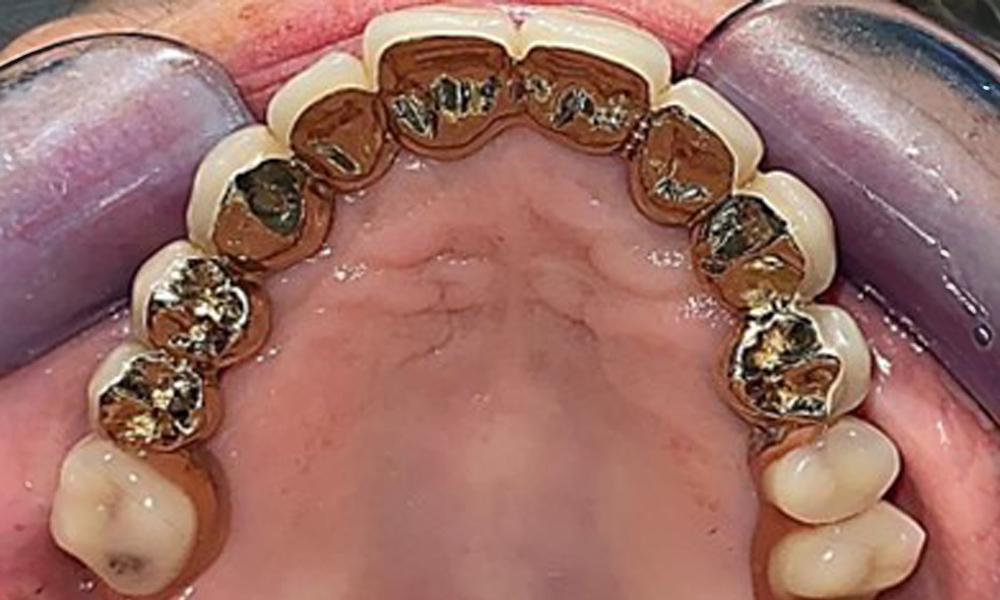

The dental findings are as follows: Combined removable implant and tooth-supported telescopic prostheses on implants 15, 13, 21, 23, 24, 25 and tooth 11 (Fig. 1, Fig. 2, Fig. 3). The patient was fitted with a fixed mandibular denture. Adequate bridges were present over 37 to 34 and 45 to 47 (Fig. 4), the crown margins were intact and there were no active caries. A composite filling with a marginal gap was present on tooth 43. There was mandibular gingival recession, exposing 1 to 3 mm of root surface. This also applies to 11.

Occlusal view: Maxilla with tooth and implant-supported telescopic prostheses.

Fig. 2: Occlusal view: Maxilla with tooth and implant-supported telescopic prostheses